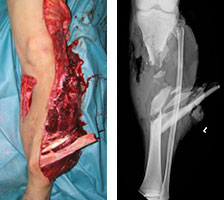

2012年の高度救命救急センター開設に伴い、重度四肢外傷・多発外傷に対して救急科および形成外科とタイアップした包括的な治療体制を拡充しています。全身管理から四肢再建までの一貫した治療戦略により高度な医療を提供しています。

近年の骨折治療の進歩のなか、さらに新しい概念を実践し骨折固定器具の開発や新しい手術方法の発展に貢献しています。